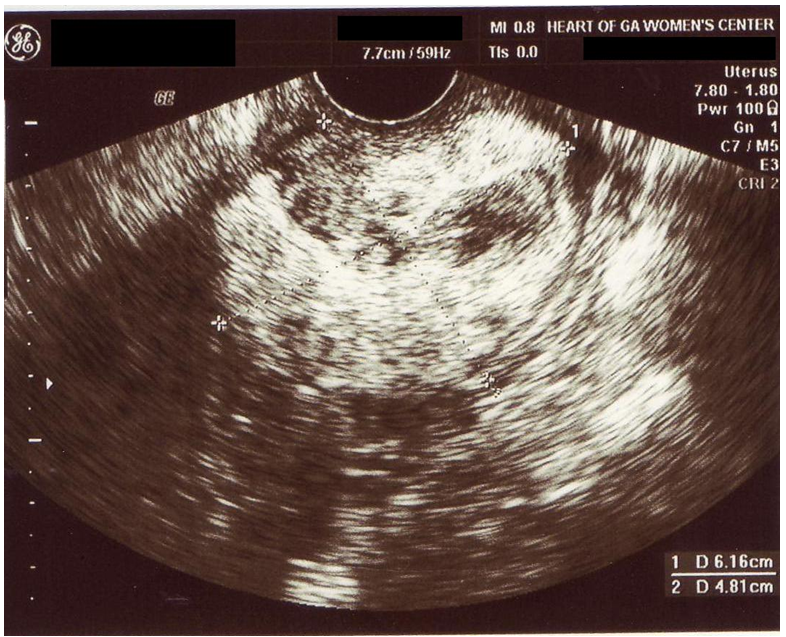

Uterine lipoleiomyoma is a rare benign tumor with an estimated incidence of 0.03% to 0.2% [1]. A 48 year-old, gravida 1 para 1, had a slowly-growing cervical mass. On ultrasound, the mass was around 5 cm in diameter and had fibroid tissue consistency with components of fat consistency (Figure 1 [Fig. 1]). On computed tomography (CT), the tumor appeared encapsulated and measured 6.2×5.2 cm with some areas of what looked like necrosis suggestive of a degenerating fibroid. No adenopathy was detected. The uterus was hypertrophic, sounding to 10 cm, and curettage showed no malignancy. After consultation with the patient, we decided to proceed with total laparoscopic hysterectomy and bilateral salpingo-oophorectomy. Operative findings included a large cervical fibroid that appeared somewhat fleshy and soft in texture (Figure 2 [Fig. 2]). First, the adhesions of the sigmoid colon to the left pelvic sidewall were taken down. The infundibulopelvic ligaments, after visualizing the ureters to be separate from them, were bilaterally coagulated and transected. The broad ligament anterior peritoneum was undermined and transected from round ligament to round ligament. The broad ligament posterior peritoneum was undermined and transected to the level of the uterosacral ligament on each side allowing the ureters to retract laterally away from the uterus, increasing the safety of the procedure. With some trouble, dissection was done to free the bladder from the cervical tumor. The vessels on the left side were then coagulated with bipolar cautery and transected with Harmonic scalpel. The cardinal ligament was taken down with Harmonic scalpel dissection. On the right side, again with difficulty the uterine vessels were skeletonized then coagulated and transected the same way as before. The cardinal ligament on this side was transected the same way. A sponge stick was placed in the anterior vagina and transverse incision was made over it and around the vagina separating it from the cervix. With the help of a tenaculum, the uterus with the cervical mass and adnexa were all removed and passed off. The operation was then continued as usual with uterosacral-cardinal-ligament suspension. Cystoscopy showed indogocarmine coming from both ureteral orifices, excluding ureteral injury. The operation was completed in 68 minutes and blood loss was approximately 150 cc. On opening of the resected tumor, no necrotic areas were noted. Pathological report showed a 258 gram uterus with a lipoleiomyoma that originated in the parametrial soft tissue along the endocervical canal near the lower uterine segment. The maximum dimension of the tumor was 5.5 cm. Incidentally, a 2.1 cm adult granulosa cell tumor was found within the parenchyma of the right ovary.

Figure 1: Ultrasound image of the cervical mass showing an echogenic mass with hypogenic components